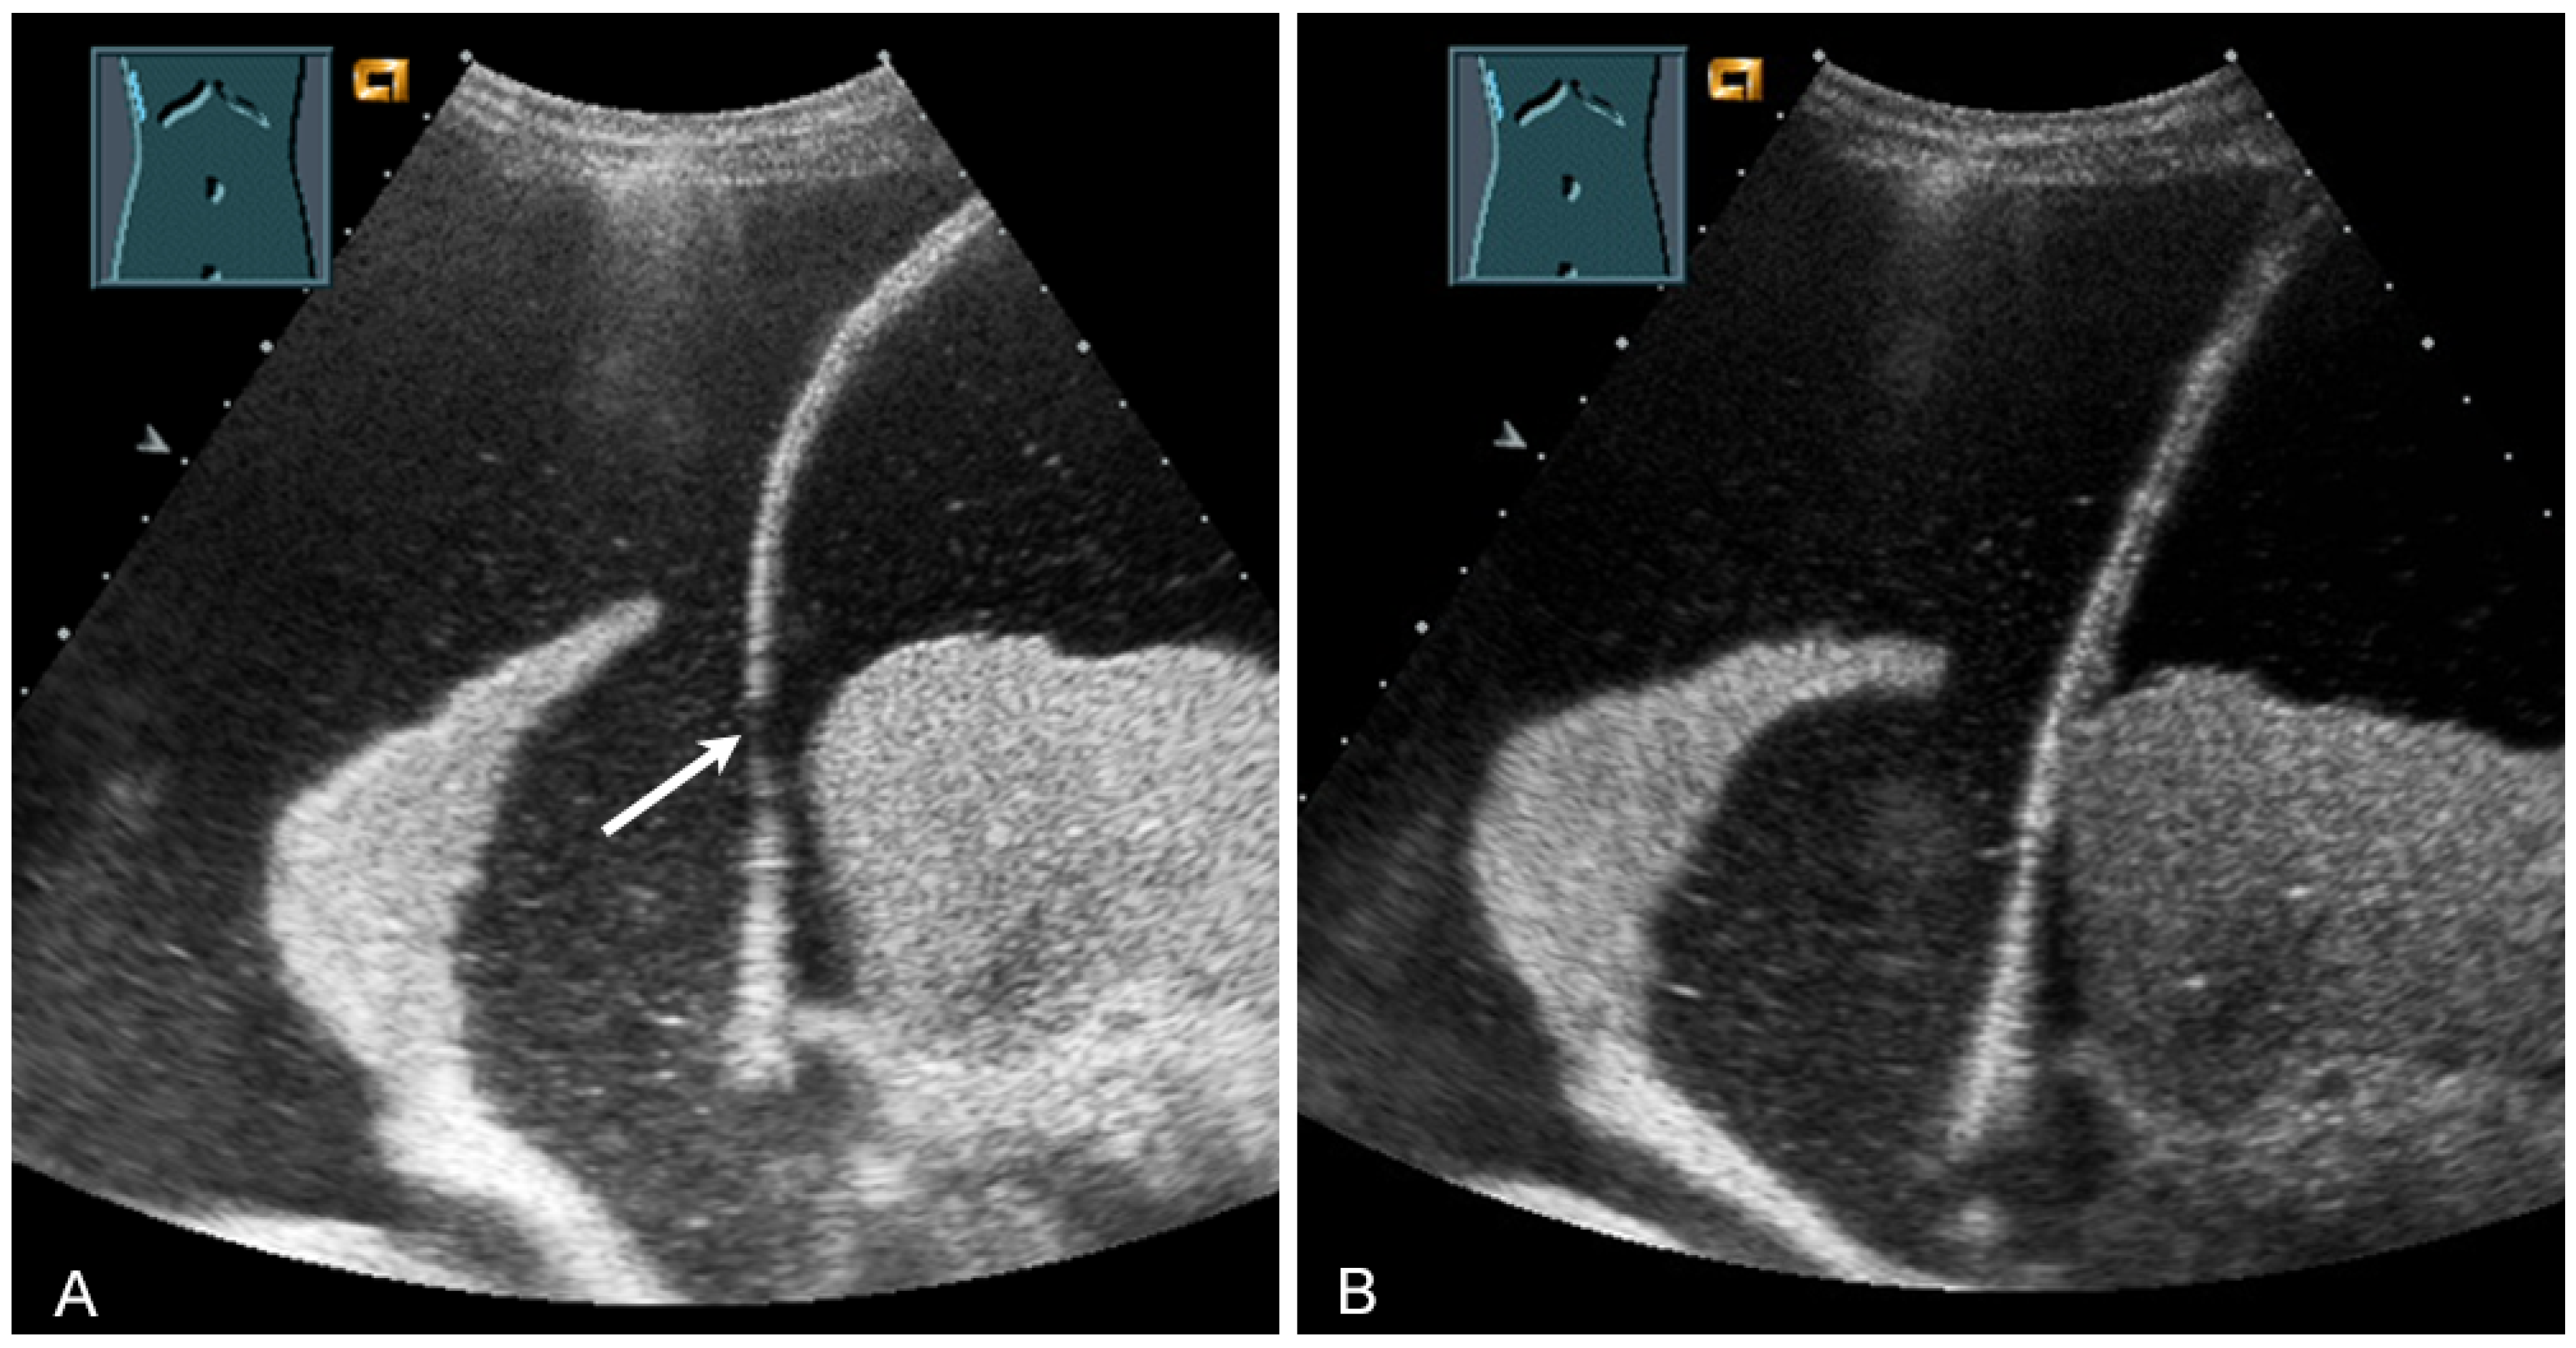

The thickness increase during inspiration was also used as a measure of muscle contraction. In most studies, an increase during inspiration of >20% is considered as normal [55] (Figure 31).

Figure 31.

Representation of diaphragm thickness in expiration (A) and inspiration (B) in pleural effusion (PE) and ascites (As).